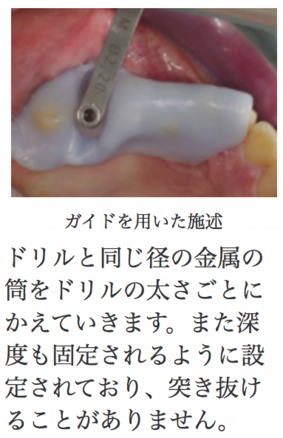

ガイドを用いたインプラントの埋入が世界的スタンダードになりつつあります。そのため当院でも上顎前歯のような審美領域や下顎臼歯など解剖学的危険エリア。またその他既存骨などの少ない骨を利用したケースでは採用をほぼ義務付けさせて頂きます。これらについて詳しくはCTによる診断が必要ですのでCTによる撮影後、必要かどうかをお伝えします。

セレックガイドシステムは毎回使い捨てパーツを使用するため、このシステムを採用する場合、

1本につき、1万円(税別)かかります。